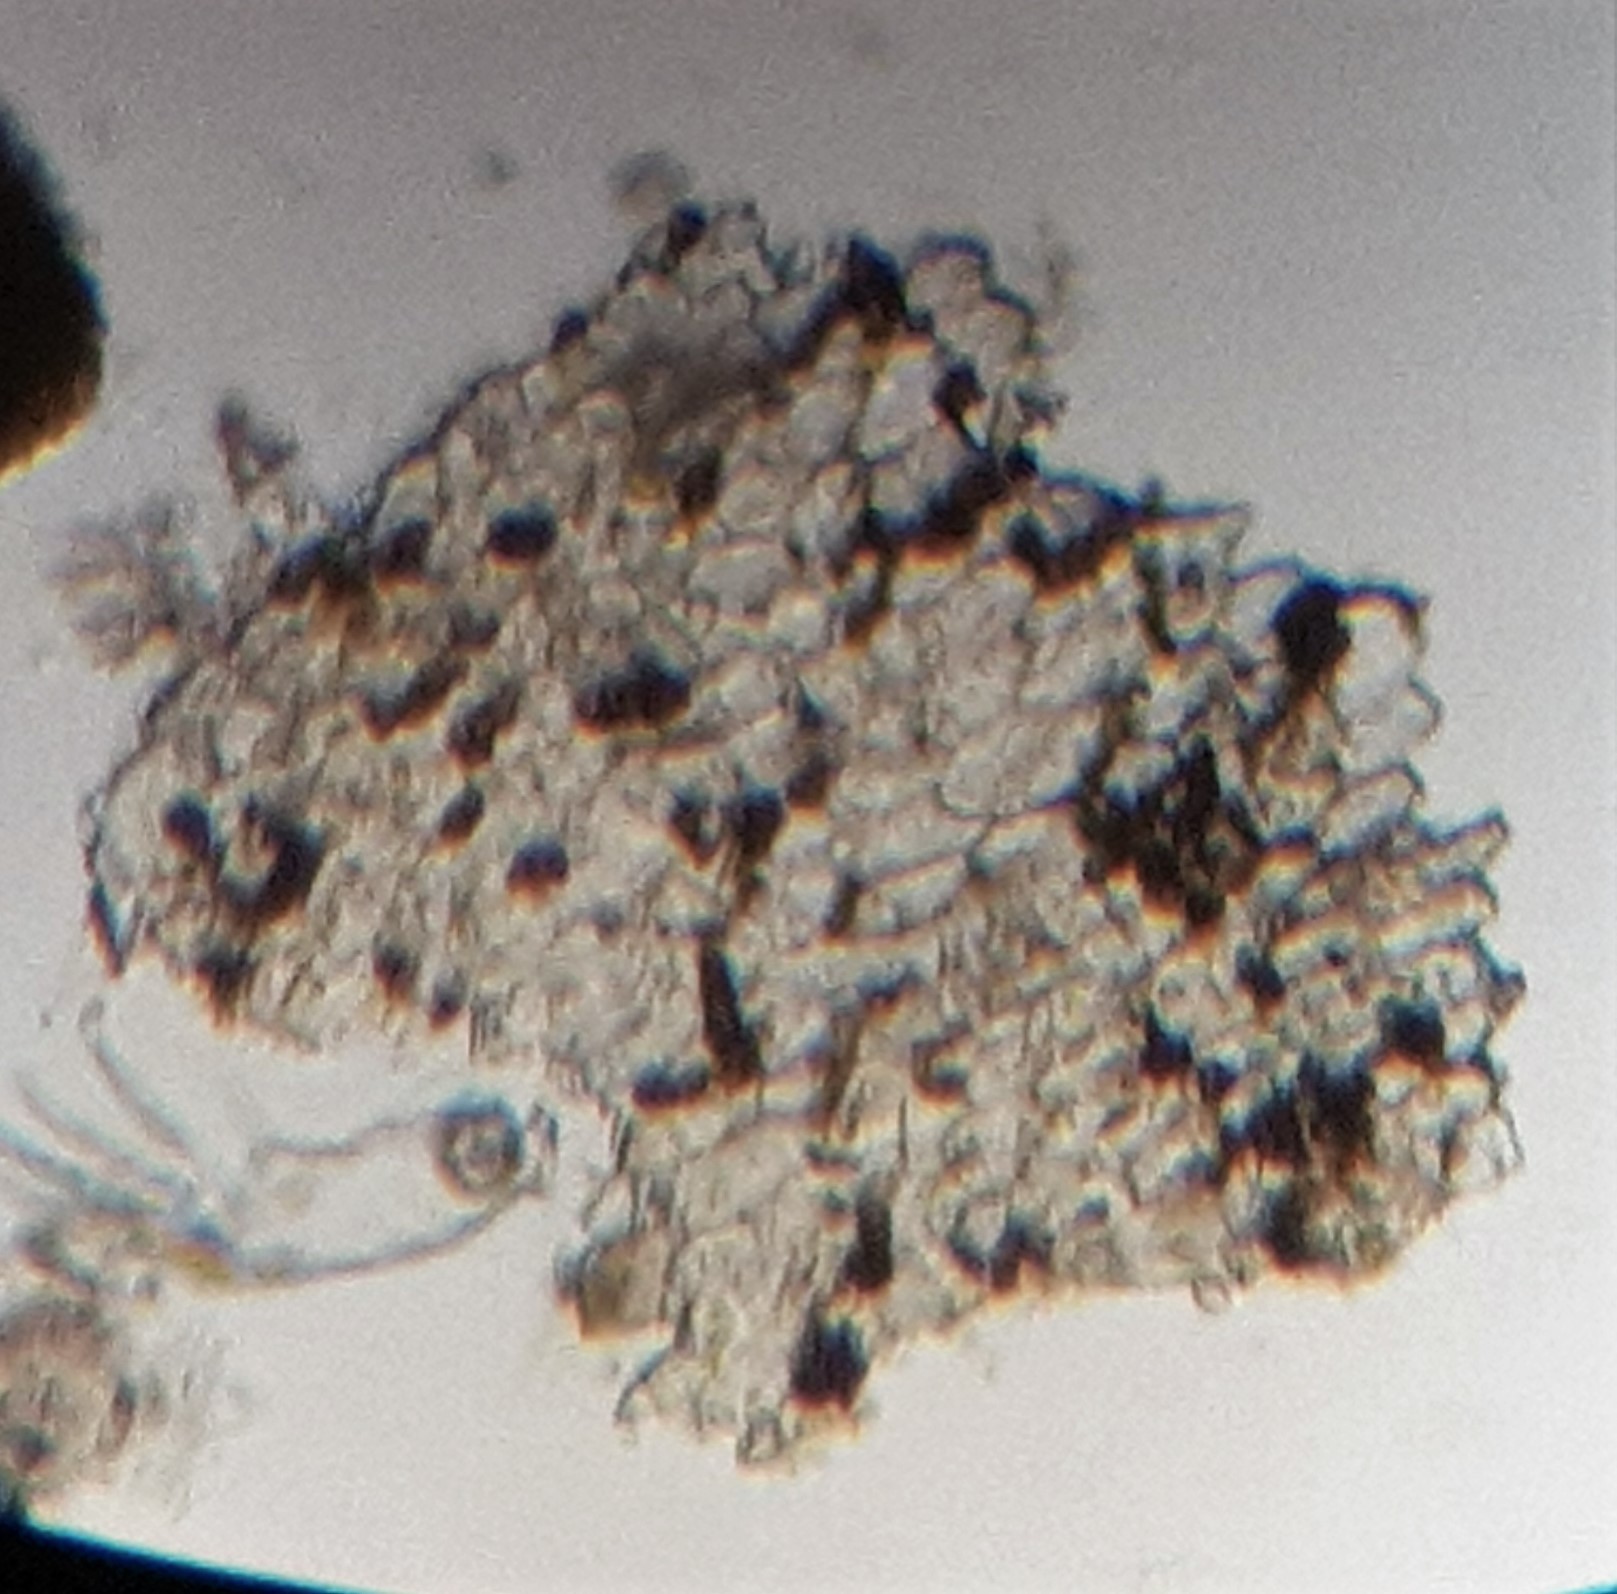

Cerva-L-03-01-07-colonia__